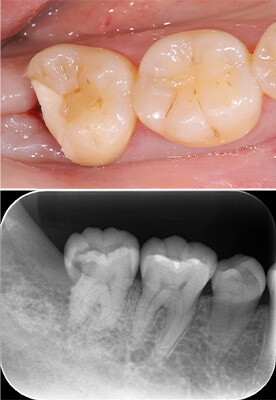

- Before

- After

技工士が歯の色に合わせて一つ一つ丁寧にセラミックインレーを製作します。